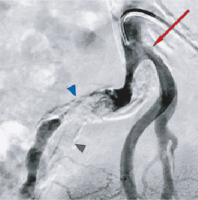

Abbildung 1: DSA-Beckenübersicht. Verschluss der A. iliaca communis rechts (roter Pfeil) und Demaskierung einer Nierenektopie mit verschlussnahem Abgang („upstream“) der Nierenarterie (weißer Pfeil), retrograde Perfusion der proximal verschlossenen A. iliaca interna (blauer Pfeil). Eine orthotope Niere kommt nicht zur Darstellung.

Abbildung 2: DSA-Angiographie der Beckenarterien rechts. Leichtgradige Stenose der Nierenarterie rechts (roter Pfeil), schwer kalzifiziertes Verschlusssegment (blauer Pfeil), Kalkschatten der verschlossenen A. iliaca interna (grauer Pfeil).